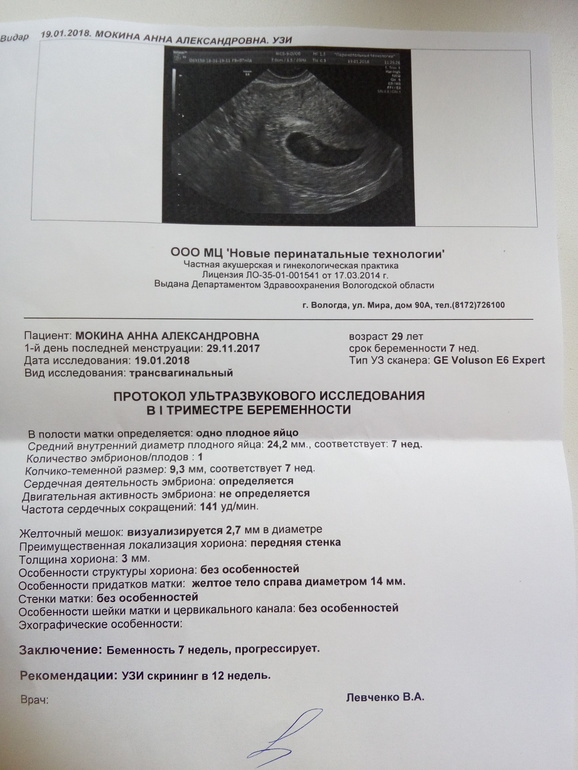

Фотографии на ранних этапах беременности